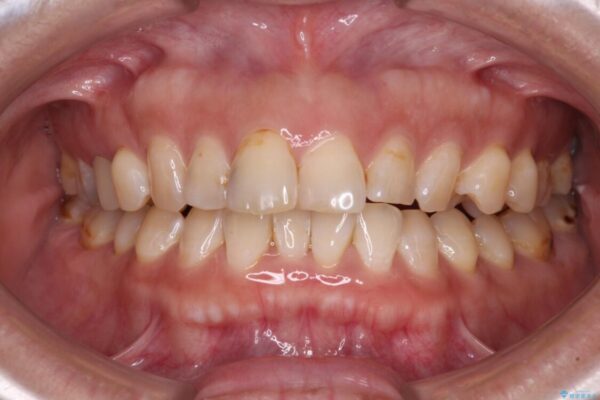

飛び出た上の前歯を気にして来院された患者様です。

なるべく早めに治療を終えたいとのことで、補助装置を用いて上顎臼歯を後方に移動させ、同時にワイヤー装置にて整えることとしました。

舌の突出癖が原因で上下の歯に大きなスペースが生じていたため、舌のトレーニングをしっかり行っていただくことで、上顎歯列をスムーズに移動させることができました。

治療後

• 【モニター】飛び出た前歯を整えたい ワイヤー矯正治療 治療後画像